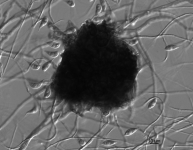

| Species Name: | Muyocopron laterale |

| Taxonomy: | FUNGI Ascomycota, Dothideomycetes, Muyocopronales, Muyocopronaceae |

| Date Received: | 2006-10-19 |

| Characters: | CULTURE CONDITIONS sporulates on tap water agar in window - // CYCLOHEXIMIDE sensitive (no growth MYC) - // HUMAN/ ANIMAL PATHOGEN arthritis of knee in immunocompetent male - Dewar CL, Sigler L, Clinical Rheumatology 29:1061-1065, 2010 // MOLECULAR SYSTEMATICS 99% ITS similarity among UAMH 8516, 8520 and 10746 - fide UAMH // THERMOTOLERANT grows best @ 25C & 35 but restricted at 42C - fide UAH (Click for publications citing UAMH 10746) |